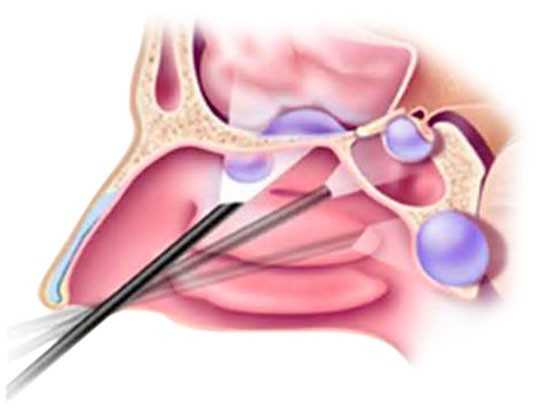

Удаление кисты в гайморовой пазухе (это наиболее распространенный вариант) может осуществляться несколькими способами:

- Обычная хирургическая операция. Классическая техника носит название операции Калдвелл-Люка. Под местным или общим наркозом под верхней губой делается разрез, передняя часть стенки пазухи вскрывается и с помощью хирургических инструментов удаляется киста. Данное лечение очень травматично. Требуется длительный период реабилитации, а полного восстановления вскрытой стенки пазухи не наступает. Отверстие зарастает не костной тканью, как было раньше, а рубцами. Из-за этого нормальное функционирование слизистой в поврежденной пазухе нарушается, что провоцирует частое появление гайморита или ринита.

- Удаление лазером. Лечение лазером обычно воспринимается людьми как самое современное, а значит, безболезненное и эффективное. Но в случае с кистой в гайморовой пазухе это мнение ошибочно. Основная проблема здесь – доступ лазерного излучения к нужному объекту. Для этого необходимо проникнуть в пазуху и обеспечить доступ к ней хирургического лазера, соответственно, нужно вскрыть стенку пазухи, как и в предыдущем методе. Из-за этих моментов лазерная операция – это не самое оптимальное лечение при обнаружении кисты.

- Эндоскопическая операция. Наиболее оптимальным является данный вид операции, поскольку доступ к кисте осуществляется через естественные отверстия в пазухах, которыми те сообщаются с полостью носа. Врач вводит в пазуху специальные приспособления, которыми осуществляет удаление кисты, а весь процесс контролируется им на мониторе. Это лечение обладает несколькими преимуществами: отсутствует проблема травматизации, не остается рубцов, сокращается срок реабилитации. Пазухи после операции снова начинают нормально функционировать.

Существуют два вида операции – эндоскопическая и классическая хирургическая операция.

Эндоскопическая операция

Эндоскопическая операция проводится без надрезов. Эндоскопическая аппаратура вместе с видеокамерой вводится в пазуху через носовой ход, далее врач выполняет эндоскопическое лечение через монитор компьютера.

Преимущества:

- эндоскопическая операция проводится быстро – в течение 10–15 минут;

- человек может уйти домой уже через несколько часов;

- эндоскопическое лечение не нарушает целостности слизистой пазухи;

- нет косметического дефекта;

- эндоскопическая операция выполняется под местным наркозом, легче переносится, чем лечение с разрезами и проколами.

Классическая операция

Классическая хирургическая операция. Делается путем надреза. Операция имеет больше недостатков, чем эндоскопическое лечение:

- больной обязательно остается под наблюдением врачей в стационаре;

- болезненные симптомы заживающего рубца;

- нарушается целостность пазухи – нет гарантии, что после операции не станут беспокоить синуситы.

- появляется дискомфорт, насморк.

Чаще всего методом локализации кисты становятся гайморовы пазухи, и удаление образования происходит следующими способами:

- Обычное хирургическое вмешательство, которое проводится под общим или местным наркозом. В области верхней губы делается разрез, вскрывается передняя часть стенки пазухи с помощью хирургических приспособлений проводиться удаление кисты. Такой способ лечения отличается повышенной травмой для пациента, и период реабилитации занимает довольно продолжительное время. Кроме этого, не происходит полного зарастания отверстия костной тканью, а лишь образуются рубцы. Все это приводит к тому, что нарушается нормальное функционирование слизистой и это приводит к частому развитию таких заболеваний, как ринит и гайморит.

- Удаление с помощью лазера является не такой уж безболезненной и эффективной процедурой, как считают многие пациенты. Это связано с тем, что имеется проблема в доступе лазерного излучения к доброкачественному образованию. Это требует проникновения в пазуху носа и обеспечение доступа к ней лазера, и добиться этого можно лишь в процессе вскрытия стенки. Именно по этой причине лазерное лечение не является оптимальным способом удаления кисты.

- Эндоскопическая операция является самым эффективным и безопасным способом удаления кисты, поскольку доступ к патологическому участку производится через естественные отверстия в пазухах носа. Специалистом проводится введение в них специальных устройств для удаления кисты и можно контролировать весь процесс с помощью монитора.

После проведенного лечения с помощью эндоскопического вмешательства не происходит рубцевания ткани, и срок восстановления не занимает много времени.